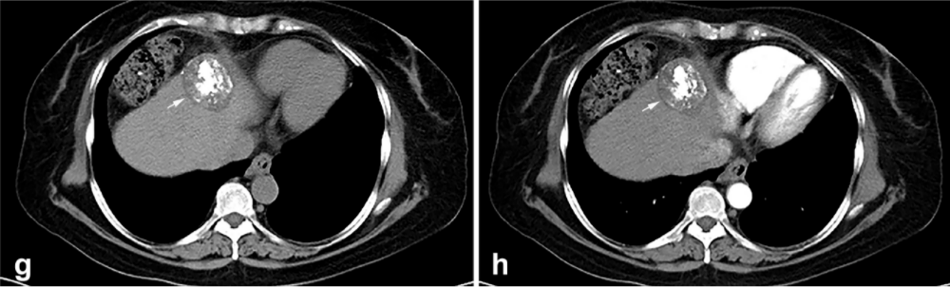

② 冷凍消融后 1 個月患者的增強(qiáng) CT 顯示HCC獲得緩解。